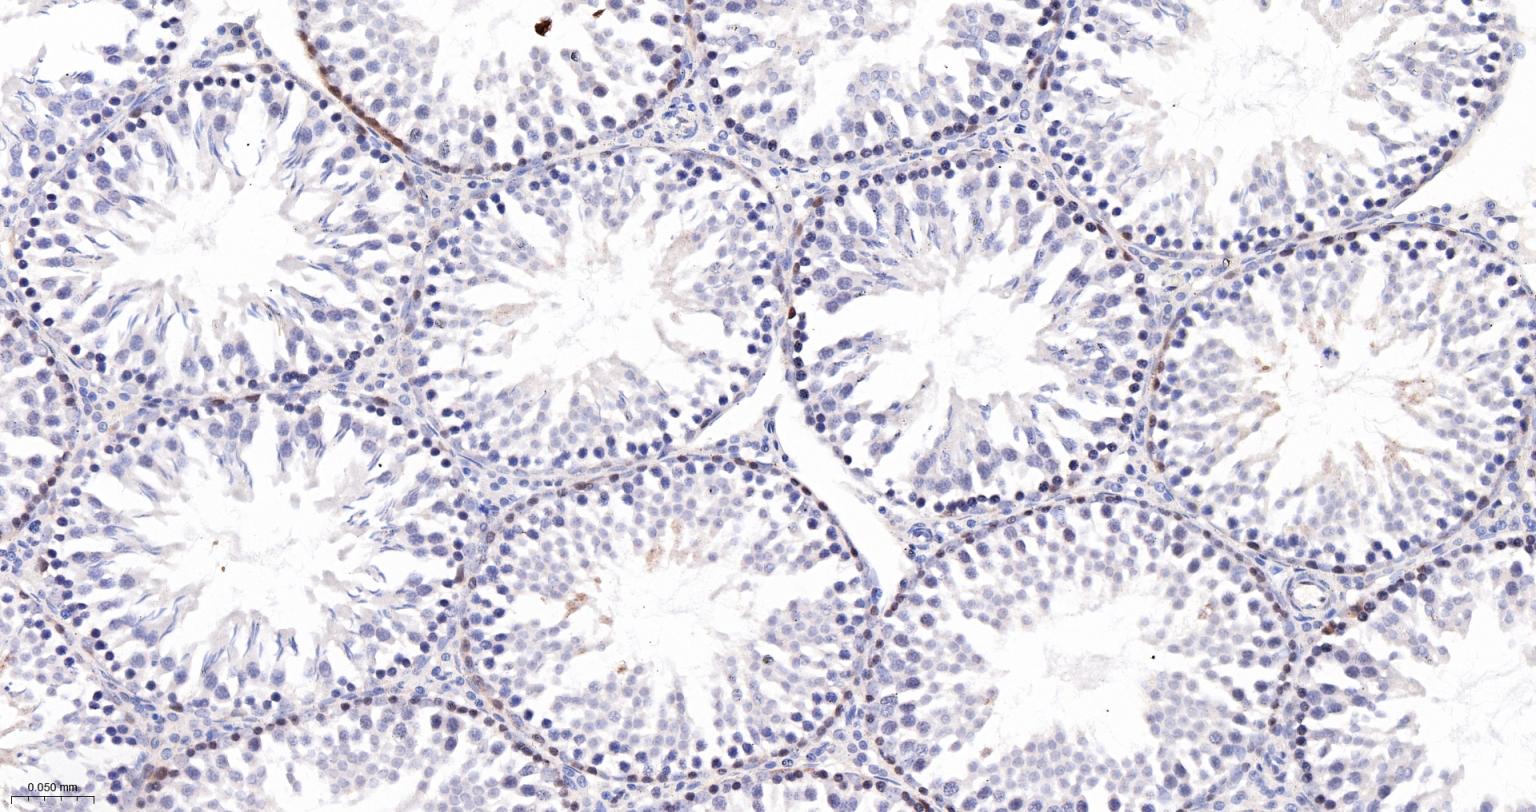

Paraformaldehyde-fixed, paraffin embedded Human Testicles; Antigen retrieval by boiling in sodium citrate buffer (pH6.0) for 15 min; The section was incubated with Caspase 2 Monoclonal Antibody, Unconjugated (bsm-61341R) at 1:200 overnight at 4°C, followed by conjugation to the bs-0295G-HRP and DAB (C-0010) staining.

Paraformaldehyde-fixed, paraffin embedded Rat Testicles; Antigen retrieval by boiling in sodium citrate buffer (pH6.0) for 15 min; The section was incubated with Caspase 2 Monoclonal Antibody, Unconjugated (bsm-61341R) at 1:200 overnight at 4°C, followed by conjugation to the bs-0295G-HRP and DAB (C-0010) staining.

Paraformaldehyde-fixed, paraffin embedded Mouse Testicles; Antigen retrieval by boiling in sodium citrate buffer (pH6.0) for 15 min; The section was incubated with Caspase 2 Monoclonal Antibody, Unconjugated (bsm-61341R) at 1:200 overnight at 4°C, followed by conjugation to the bs-0295G-HRP and DAB (C-0010) staining.